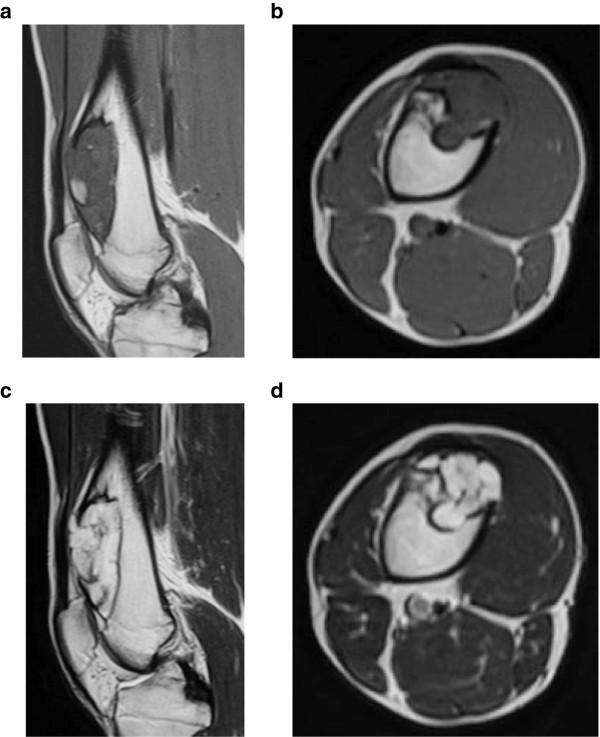

Periosteal chondromas are rare benign cartilaginous tumors that arise adjacent to the cortex beneath the periosteum. These lesions are usually slow-growing and rarely exceed 3 cm in the greatest dimension. Here, we describe a 17-year-old boy who had a giant periosteal chondroma of the right distal femur, which was treated with intralesional resection and intensive curettage. In addition, we report a novel application of a bioresorbable plate in the management of the large bone defect after resection of a benign bone tumor.